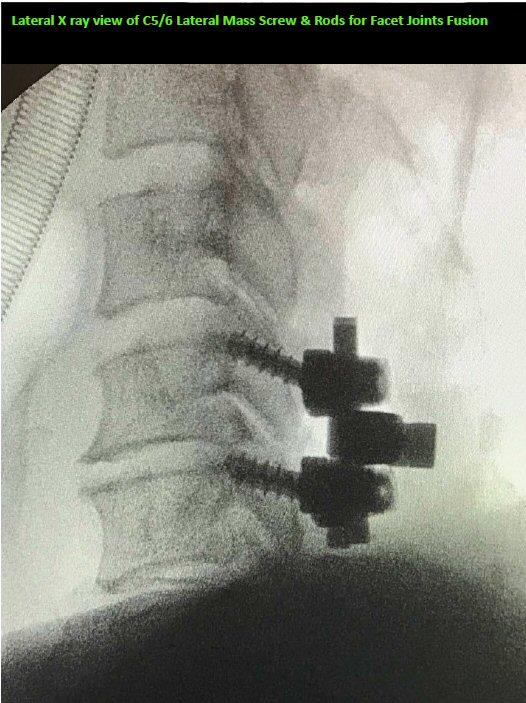

我一直在为你考虑及选择最好的手术方案。 我认为这个手术选项最适合你,因为你的C5 / 6小关节是非常不稳定, 这是我手术前的预测和手术期间显微镜下的确认

当你从麻醉药中醒来时,你问我如何评价我对这次手术结果的满意程度(100分为满分)。 我回答: 99分,因为你颈椎不稳定及疼痛导致你逃不了镶嵌螺丝的颈椎融合手术, 不过你只是需要一节C5/6颈椎的融合!于C3至C5颈椎,我只做了椎板切除的神经减压术。